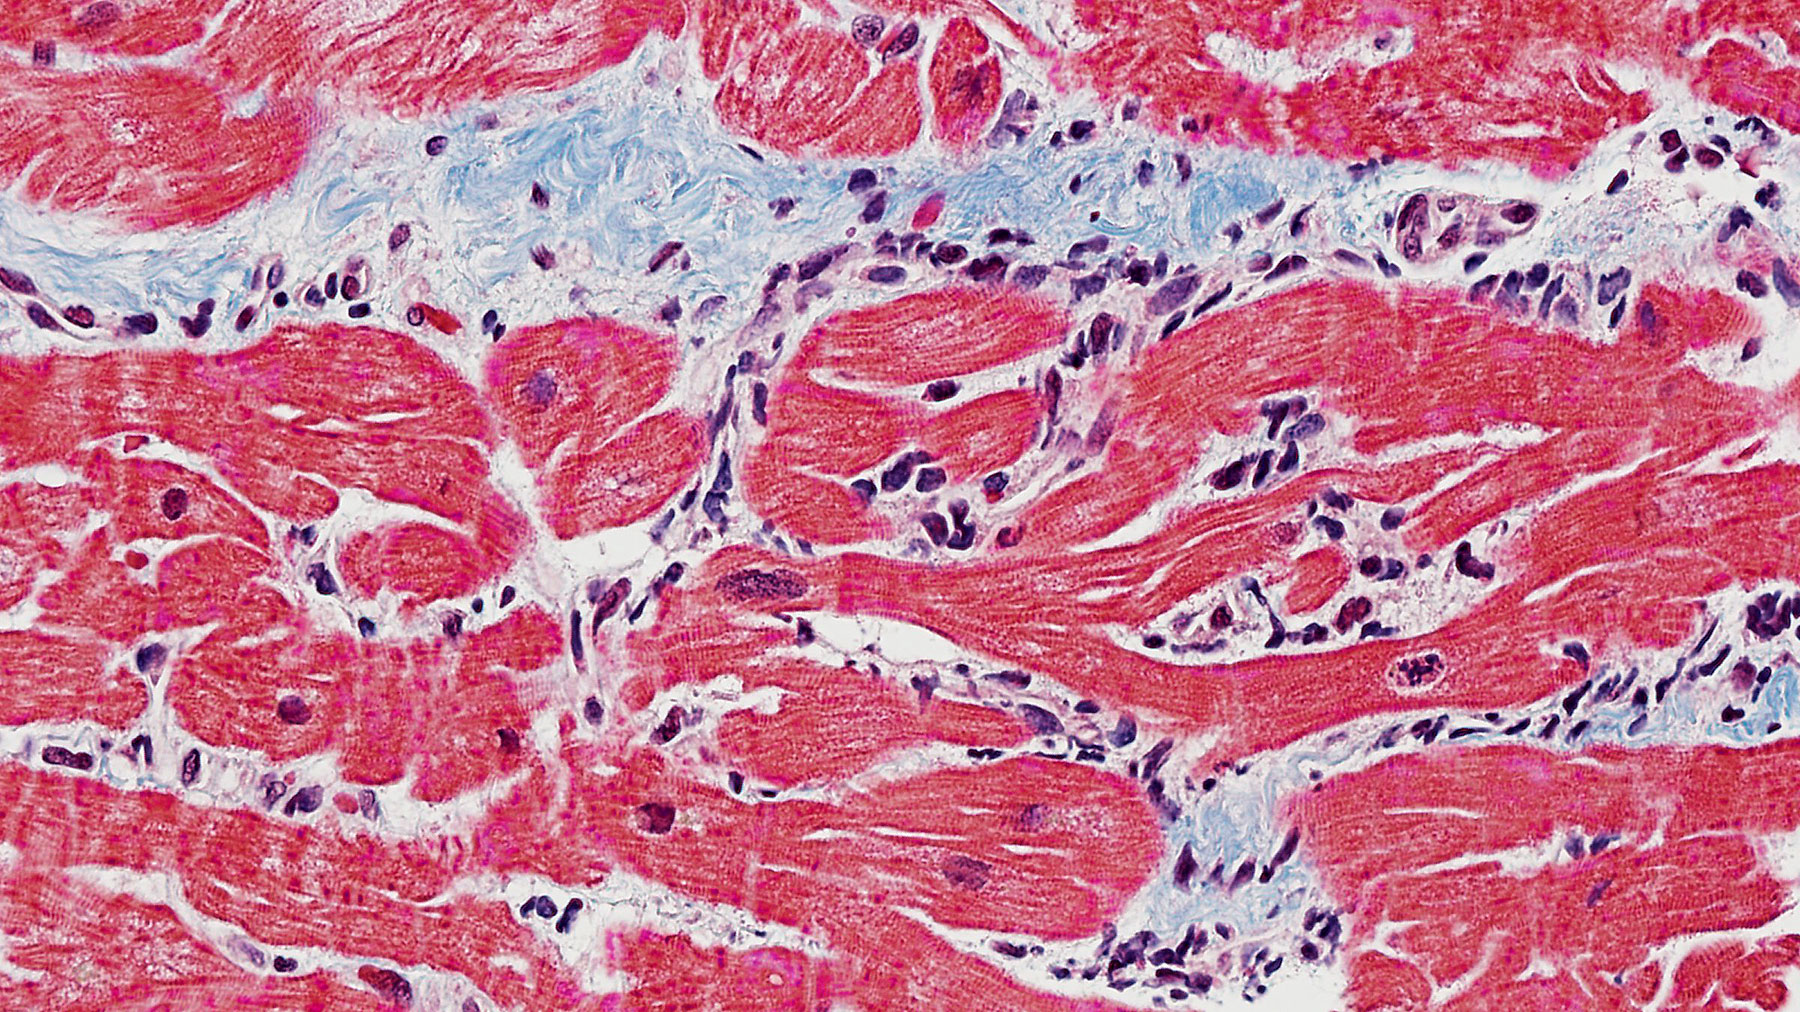

Figure C. H&E x40

Figure D. Trichrome stain x40

Figure E. H&E x40

Figure F. Trichrome stain x40

Histology: Images for suboptimal biopsy (Figure A) and normal myocardial tissue from a different heart allograft (Figure B) are presented as references.  Patient's sections with H&E staining (Figures C & E) show perivascular mononuclear cell infiltration with a single focus of associated myocyte damage consistent with mild acute cellular rejection, ISHLT 2004 Grade 1R (ISHLT 1990 Grade 1A). Trichrome staining from consecutive sections from C & E (Figures D & F) reveal mild interstitial edema.